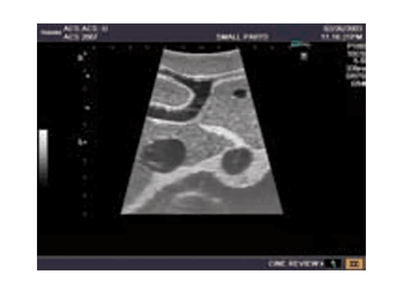

Das Ultraschall-Modell für Sonografie ist speziell für die Ausbildung von Anfängern und die Demonstration durch Fachleute konzipiert. Es bietet eine detaillierte und realistische Darstellung der Anatomie des Abdomens, einschließlich der Leber, Gallenwege, des Pankreas und der Nieren. Das Modell erfüllt die höchsten Anforderungen an eine exzellente Ausbildung und ermöglicht die Durchführung von offenen intraoperativen Sonografien sowie laparoskopischen Untersuchungen, um etwaige Läsionen und Steinbildungen zu prüfen. Es umfasst eine Vielzahl von Läsionen wie Gallensteine, Zysten und Tumore, die in den verschiedenen Organen simuliert sind, um realistische Übungsmöglichkeiten zu bieten.

Simulierte Läsionen (solide Tumore, Zysten, Gallensteine) in wichtigen Organen für praxisnahe Ausbildung

Die Simulation von pathologischen Befunden wie Tumoren, Zysten und Steinbildungen ermöglicht eine umfassende Vorbereitung auf die Ultraschalldiagnostik